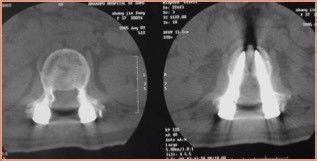

诊断:腰2椎体爆裂性骨折(AO分型:A3.1) 治疗:给予急诊行腰1-腰2椎弓根钉固定+骨折复位术。术中行椎板切除减压,用骨冲将突入椎管的骨块复位。

术后1年拆除内固定,复查骨折无明显高度丢失。